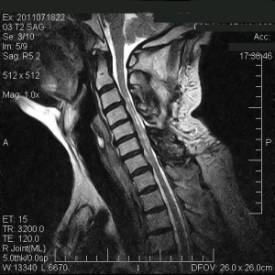

Resonancia Magnética: es el método de elcción para los pacientes con mielopatía cervical. Además de dar una evaluación del grado de estenosis del canal espinal, la Resonancia Magnética puede identificar mielomalacia o lesiones medulares (mielopatía).